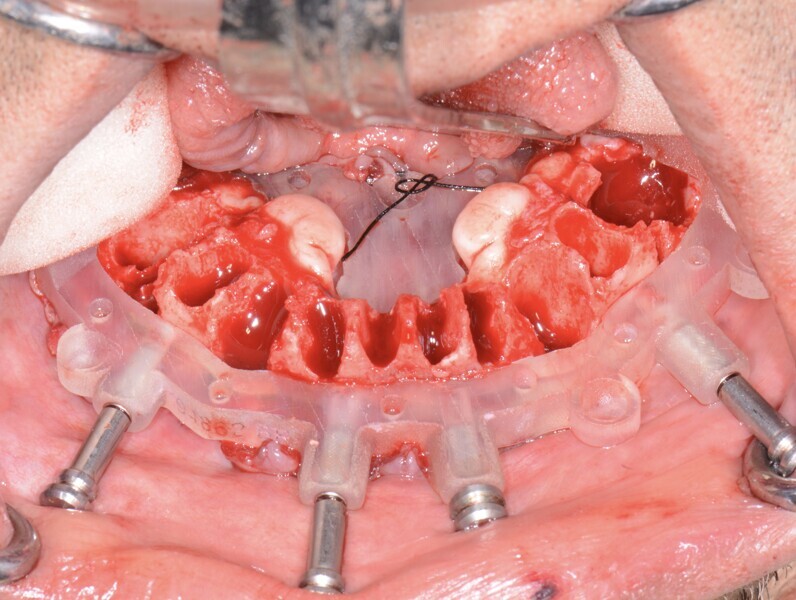

Fig. 16: Mandibular bone levelling guide.

Fig. 17: Mandibular implant surgical

guide.